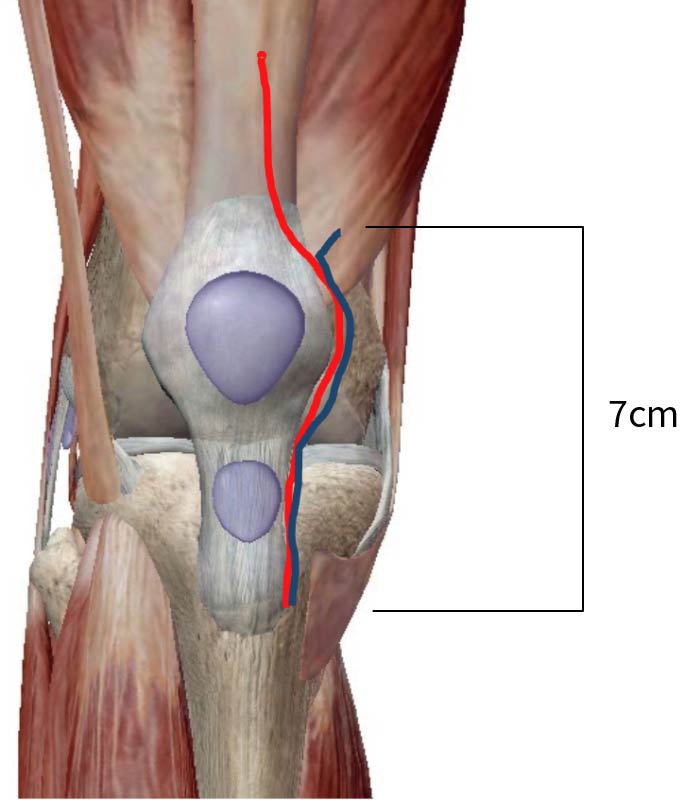

変形性膝関節症に対する人工膝関節置換術後の理学療法 - YouTube,

変形性膝関節症に対する人工膝関節置換術後の理学療法 - YouTube, 極める変形性膝関節症の理学療法: 保存的および術後理学療法の,

極める変形性膝関節症の理学療法: 保存的および術後理学療法の, 人工膝関節置換術後のリハビリテーション | 医療法人社団豊正会,

人工膝関節置換術後のリハビリテーション | 医療法人社団豊正会, 膝関節の症状や痛みの原因、最新の手術方法について医師が徹底解説,

膝関節の症状や痛みの原因、最新の手術方法について医師が徹底解説, エビデンスに基づいた人工膝関節置換術後の理学療法|PT-OT-ST.NETJLCから出ている“変形性膝関節症に対する人工膝関節置換術後の理学療法“のDVDです(o^^o)一度視聴したのみの美品です♡PT、PTSにお勧めなDVDです◎

エビデンスに基づいた人工膝関節置換術後の理学療法|PT-OT-ST.NETJLCから出ている“変形性膝関節症に対する人工膝関節置換術後の理学療法“のDVDです(o^^o)一度視聴したのみの美品です♡PT、PTSにお勧めなDVDです◎